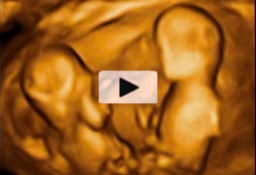

Ecografía 4D de gemelos moviéndose

Ecografía 4D de gemelos de 12 semanas moviéndose: los hermanos "juegan" al fútbol En esta ecografía 4D, que corresponde a gemelos, podemos observar el curioso movimiento de los hermanos, que parecen estar jugando al fútbol. La realidad es que los niños se mueven por estimulación. A veces...